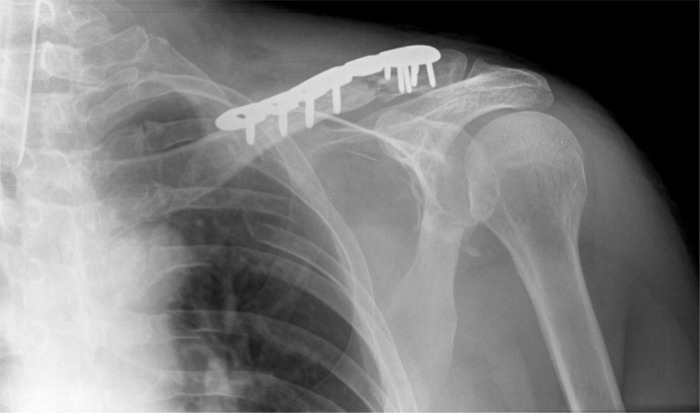

Наиболее типичная травма в сноуборде — перелом запястья. Бывают также растяжения запястья, ушибы и вывихи локтя. Кроме того, риску подвержены плечевой пояс и ключица. Нередки сотрясения мозга и другие травмы головы и шеи.